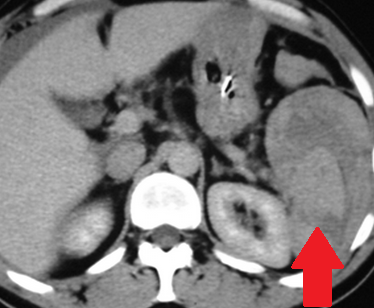

Αυτόματη ρήξη/αιμορραγία νεφρού — αγγειομυολίπωμα (Ευγενική παραχώρηση Dr. V. Penopoulos)